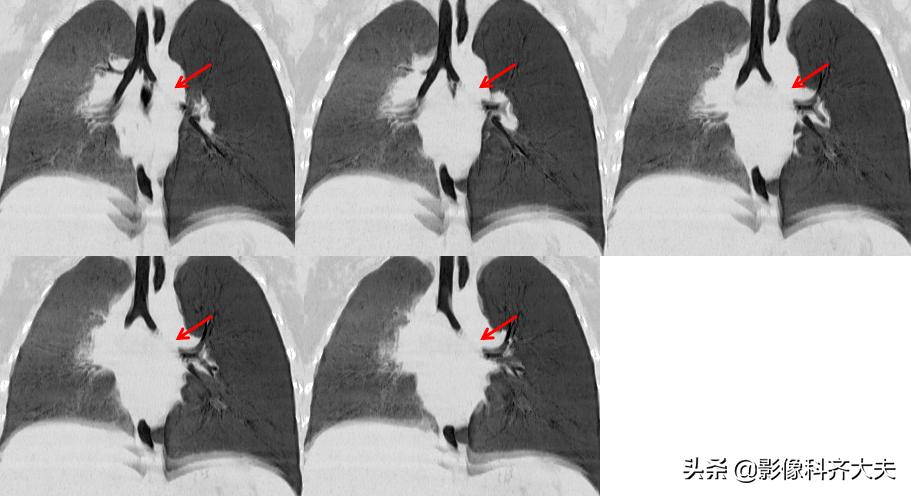

病例2、病史:患儿,男、1岁9个月,咳喘20天。家属否认异物吸入史。

图为正位普通X线片,显示左侧明显肺气肿改变,提示左侧支气管异物可能,因家属否认异物吸入,遂进一步做CT确诊。

CT冠状位重建明确显示左侧自气管阻塞,有明确异物的存在,红色箭头所示。

病例3、病史:患儿,两岁半。咳嗽近一个月,外院按支气管炎治疗半个月无好转。询问家属是否有吃东西呛咳病史,家属回忆一个月前还在好像吃过花生,瓜子,但不能完全确定。

图像显示在气管分叉的位置有一“瓜子”形异物的存在,尤其是冠状位显示更明显。